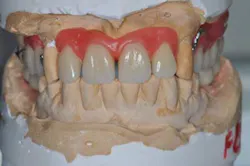

Figs. 3a, b, and c: Extraction of the upper incisors and maxillary removable acrylic placement

- Provisional acrylic removable partial denture placement after the extractions of the upper teeth. It serves as a functional and esthetic test for the rest of the treatment.